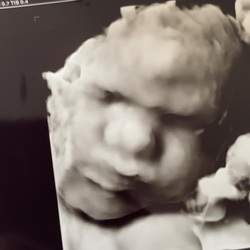

Ik ben nu 14 weken zwanger en sinds 2 weken ook last van bloed verlies, roze/bruine afscheiding. Heb toen meteen een echo gehad en de tweede keer mocht ik extra hartje laten luisteren. Tijdens de echo kwamen we er achter dat mijn placenta laag ligt en hierdoor dus kleine bloedingen kunnen ontstaan. Als ik nog een keer helder rood bloed krijg wordt ik doorgestuurd naar de gynaecoloog, dat is vooral om andere dingen uit te sluiten. De kleine doet het goed en spartelt lekker rond in mijn buik.

Dinsdag heb ik weer een echo en zal weer opgelucht zijn als ik ons kleine kersje weer kan zien.